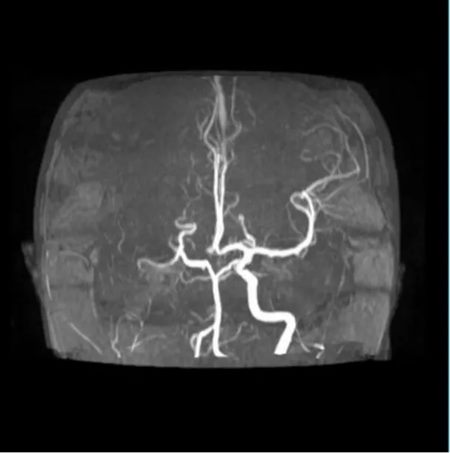

神经内科评估、神经外科接力、影像瞬间出片……

最终决定:脑血管造影 + 经皮颅内动脉取栓术。

手术台上,团队从她堵塞的颈内动脉中,取出一条近10厘米长的血栓。